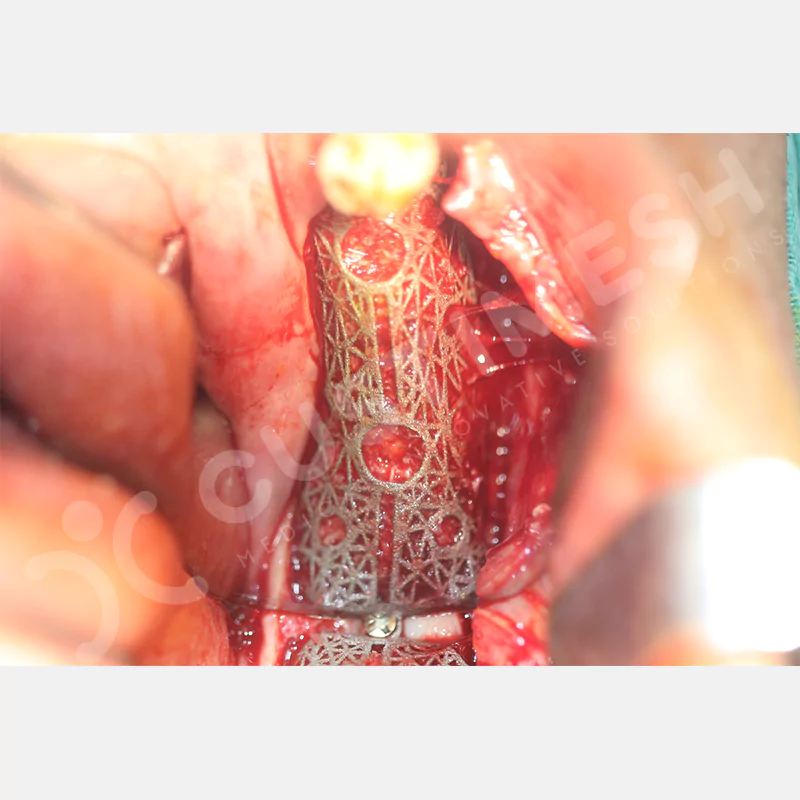

Medikal sınıf titanyumdan, hastanın bilgisayarlı tomografi verileri kullanılarak CAD yazılımlarıyla tasarlanan ve 3D baskı teknolojisiyle üretilen bu yenilikçi çözüm, özellikle kompleks kemik defektlerinde standart meshlerin sağlayamadığı üstün mekanik stabilite ve mükemmel adaptasyon özellikleri sunar. Anatomik yapıya tam uyum sağlayarak greft materyalinin yerinde kalmasını garanti ederken, optimal vaskülerizasyonu destekleyerek kemik rejenerasyon sürecini hızlandırır.

- Özel Olarak Tasarlanmış İmplant ve Kondenzasyon Delikleri

- Palatinal Yada Lingualden Vidalama İhtiyacı Olmaması

VAKA 1

VAKA 2

VAKA 3